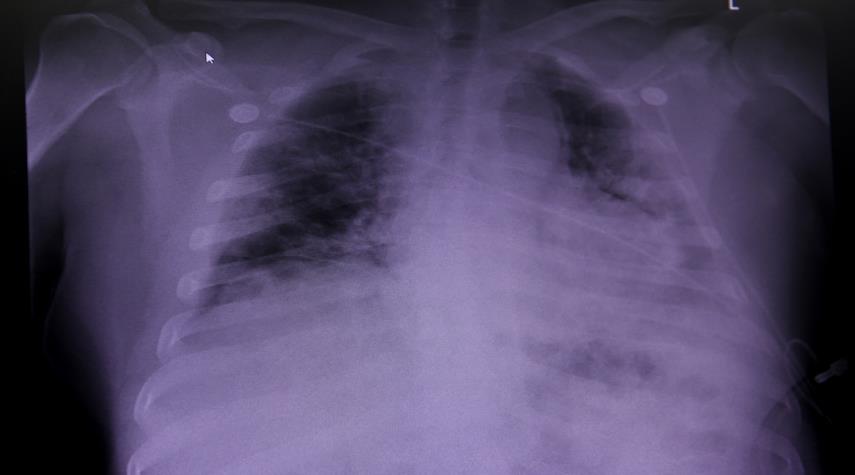

كورونا وسرطان الرئة.. التشابه والاختلاف

منوعات_الكوثر: كشف رئيس الجمعية البريطانية لمكافحة أمراض السرطان، روبرت رينتولا، عن التشابه والاختلاف بين أعراض الإصابة بفيروس كورونا وسرطان الرئة.